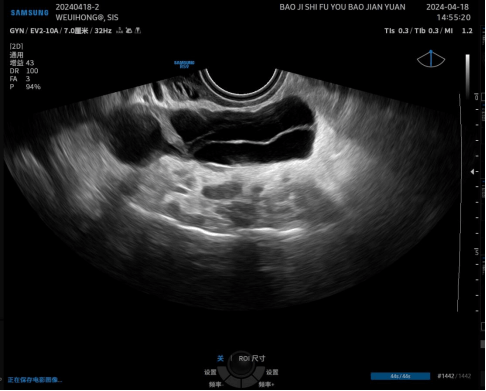

病例再现 / 02

宫腔水造影可以显示二维超声看不见的瘢痕部憩室。